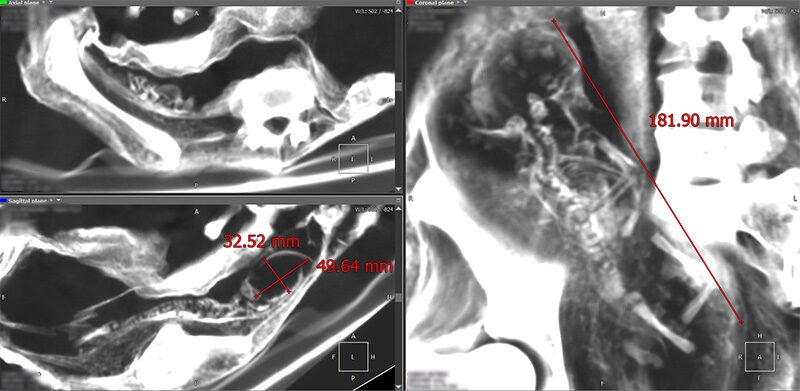

骨の構造を調べると、人間の場合上腕部は橈骨と尺骨、下肢も脛骨と腓骨という二本の骨で構成されているのに対し、このタイプは上腕も下肢も一本の棒のような骨しか持っていない。女性と思われる個体の体内には、卵らしき楕円形の物体が確認されており、その多くに金属片が埋め込まれている。

ジャミンが「ホセフィーナ」を入手したのは2017年4月のことで、身長58.5センチ。下腹部が少し膨らんでおり、X線撮影の結果体内に、卵と思われる3つの楕円形の物体が見つかっている。卵の形は鳥類と異なり、爬虫類のものに似ている。胸には金属板が埋め込まれており、成分を分析したところ銅が85%だという。

これは身長49センチと小さく、手足の指は3本で、頭の形は人間・爬虫類型よりもハイブリッドに似ているが、体型はまったく異なる。胴体は長い棒のような構造で、足の付け根から下に腹部が続いており、内部に卵形の物体が2つ確認されている。身体全体に10の金属片が埋め込まれており、背中には小さな羽根のようなものもある。この「ヌカリ」については、「エイリアン・プロジェクト」のサイトにも、まだ詳しい情報は掲載されていない。